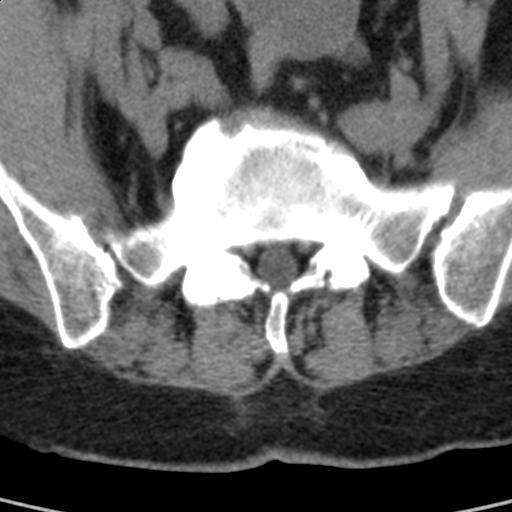

患者;女性;左下肢疼痛。

l5s1显示椎间盘突出,椎体边缘骨质增生,双侧黄韧带钙化。(请上传骨窗)

l5s1显示椎间盘突出,椎体边缘骨质增生,双侧黄韧带钙化 ,两侧椎小关节肥大,关节面硬化,关节间隙变窄,提示:椎小关节综合症

双侧的侧隐窝有狭窄。

我认为应该考虑为:l5s1椎间盘膨出,余(椎小关节退变、黄韧带钙化、椎间孔狭窄)与各位同行无异议。

l5s1显示椎间盘膨出,突出,椎体边缘骨质增生向后压迫硬膜囊,双侧黄韧带钙化,小关节面综合征

l4-5椎间隙略窄,应该扫描。

l5s1椎间盘向后脱出使脊膜囊受压,椎体边缘骨质增生,双侧黄韧带钙化。l45椎间盘估计亦突出,为何未扫。